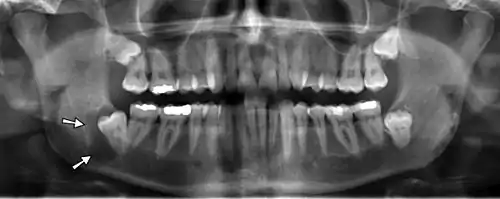

| Panoramic radiograph | |

![]() A dental panoramic radiograph, showing the maxilla and mandible, all the teeth including the "wisdom teeth," the frontal and maxillary sinuses, the nasal cavity and the temporomandibular joint and other near by head and neck anatomy. | |

A panoramic radiograph is a panoramic scanning dental X-ray of the upper and lower jaw. It shows a two-dimensional view of a half-circle from ear to ear. Panoramic radiography is a form of focal plane tomography; thus, images of multiple planes are taken to make up the composite panoramic image, where the maxilla and mandible are in the focal trough and the structures that are superficial and deep to the trough are blurred.